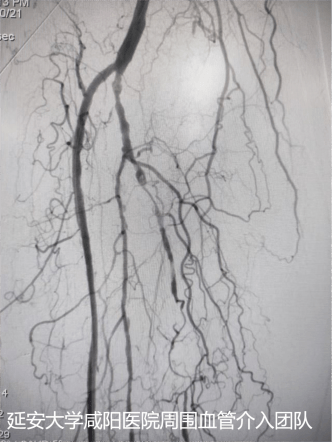

術(shù)后DSA

為了保肢,輾轉(zhuǎn)至我院心血管內(nèi)科一病區(qū),吳棟梁副院長(zhǎng)帶領(lǐng)周圍血管病介入團(tuán)隊(duì)討論、經(jīng)評(píng)估及術(shù)前準(zhǔn)備后于3月24日對(duì)患者進(jìn)行下肢動(dòng)脈球囊擴(kuò)張成形術(shù),術(shù)中下肢動(dòng)脈造影提示膝下脛前、脛后、腓動(dòng)脈動(dòng)脈閉塞,血管鈣化嚴(yán)重及側(cè)支血管形成較差(股腘動(dòng)脈病變TASC II分型為D型);手術(shù)難度較大,手術(shù)失敗患者直接面臨截肢,在規(guī)范化的介入操作下最終開(kāi)通患肢閉塞血管,術(shù)后肢體缺血癥狀立即改善,足背動(dòng)脈搏動(dòng)恢復(fù);下肢變暖了,疼痛消失了,老爺子及家屬終于舒展開(kāi)了愁眉,露出了久違的笑容。